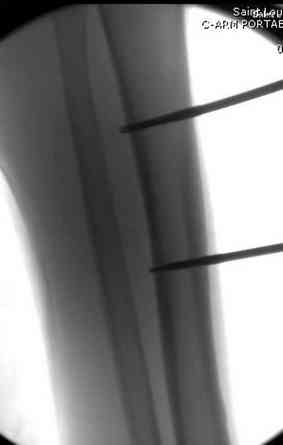

После пары Irrigation& Debridment с вакуумом можно провести окончательную фиксацию интрамедуллярным методом. Чем быстрее, тем лучше, потому что сроки нахождения наружных фиксаторов на конечности тоже имеют значение, риск осложнения увеличивается после длительного пребывания наружного фиксатора.

Открытые переломы, если имеется хороший доступ из раны можно сопоставить и зафиксировать первично пластиной, потому что несопоставленные переломы намного труднее репонируется в поздние сроки. Активизация больного за счет стабилизации кости благоприятно влияет на сращение, а также облегчается манипуляция по закрытию дефекта.

здесь случай с политравмой, перелом зафиксирован наружным фиксатором, после третьей irrigation&debridment фиксация бедра пластиной с последующей кожной пластикой.